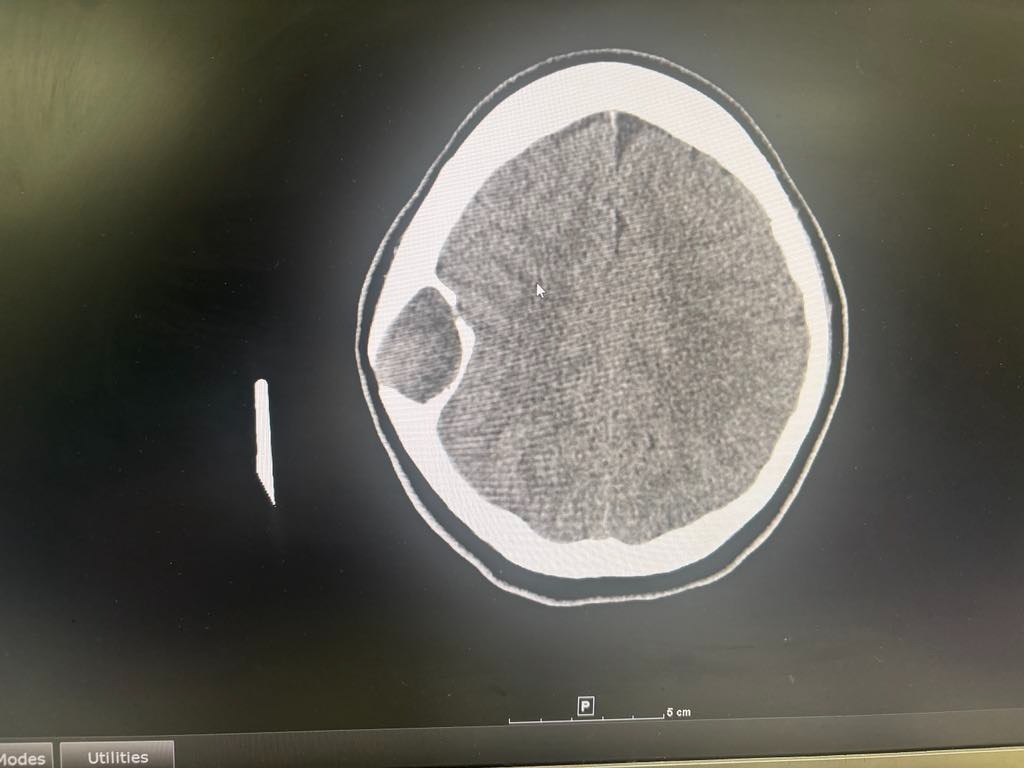

Since January, she’s been battling nonstop headaches, dizziness, and blurry vision. She’s been in and out of doctor’s offices and hospitals with no real answers—just a lot of waiting rooms, medical bills, and frustration.

A few days ago, things got worse, and she went to the ER. They did a CT scan and told her they’d refer her to a neurosurgeon… eventually. But Kaylee wasn’t about to sit around and wait while her head was pounding. So she marched herself straight to OSU. Within an hour, they admitted her to The James Cancer Hospital.

It’s a benign bone tumor in her skull bone—something she was born with—and it CAN be removed.